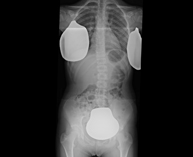

- RX Abdomen

Técnica mediante la cual, utilizando rayos X, se obtienen imágenes del abdomen (estómago, intestino delgado, intestino grueso, hígado, riñones, vejiga, pelvis ósea, etc.) para su estudio. - RX Columna lumbar